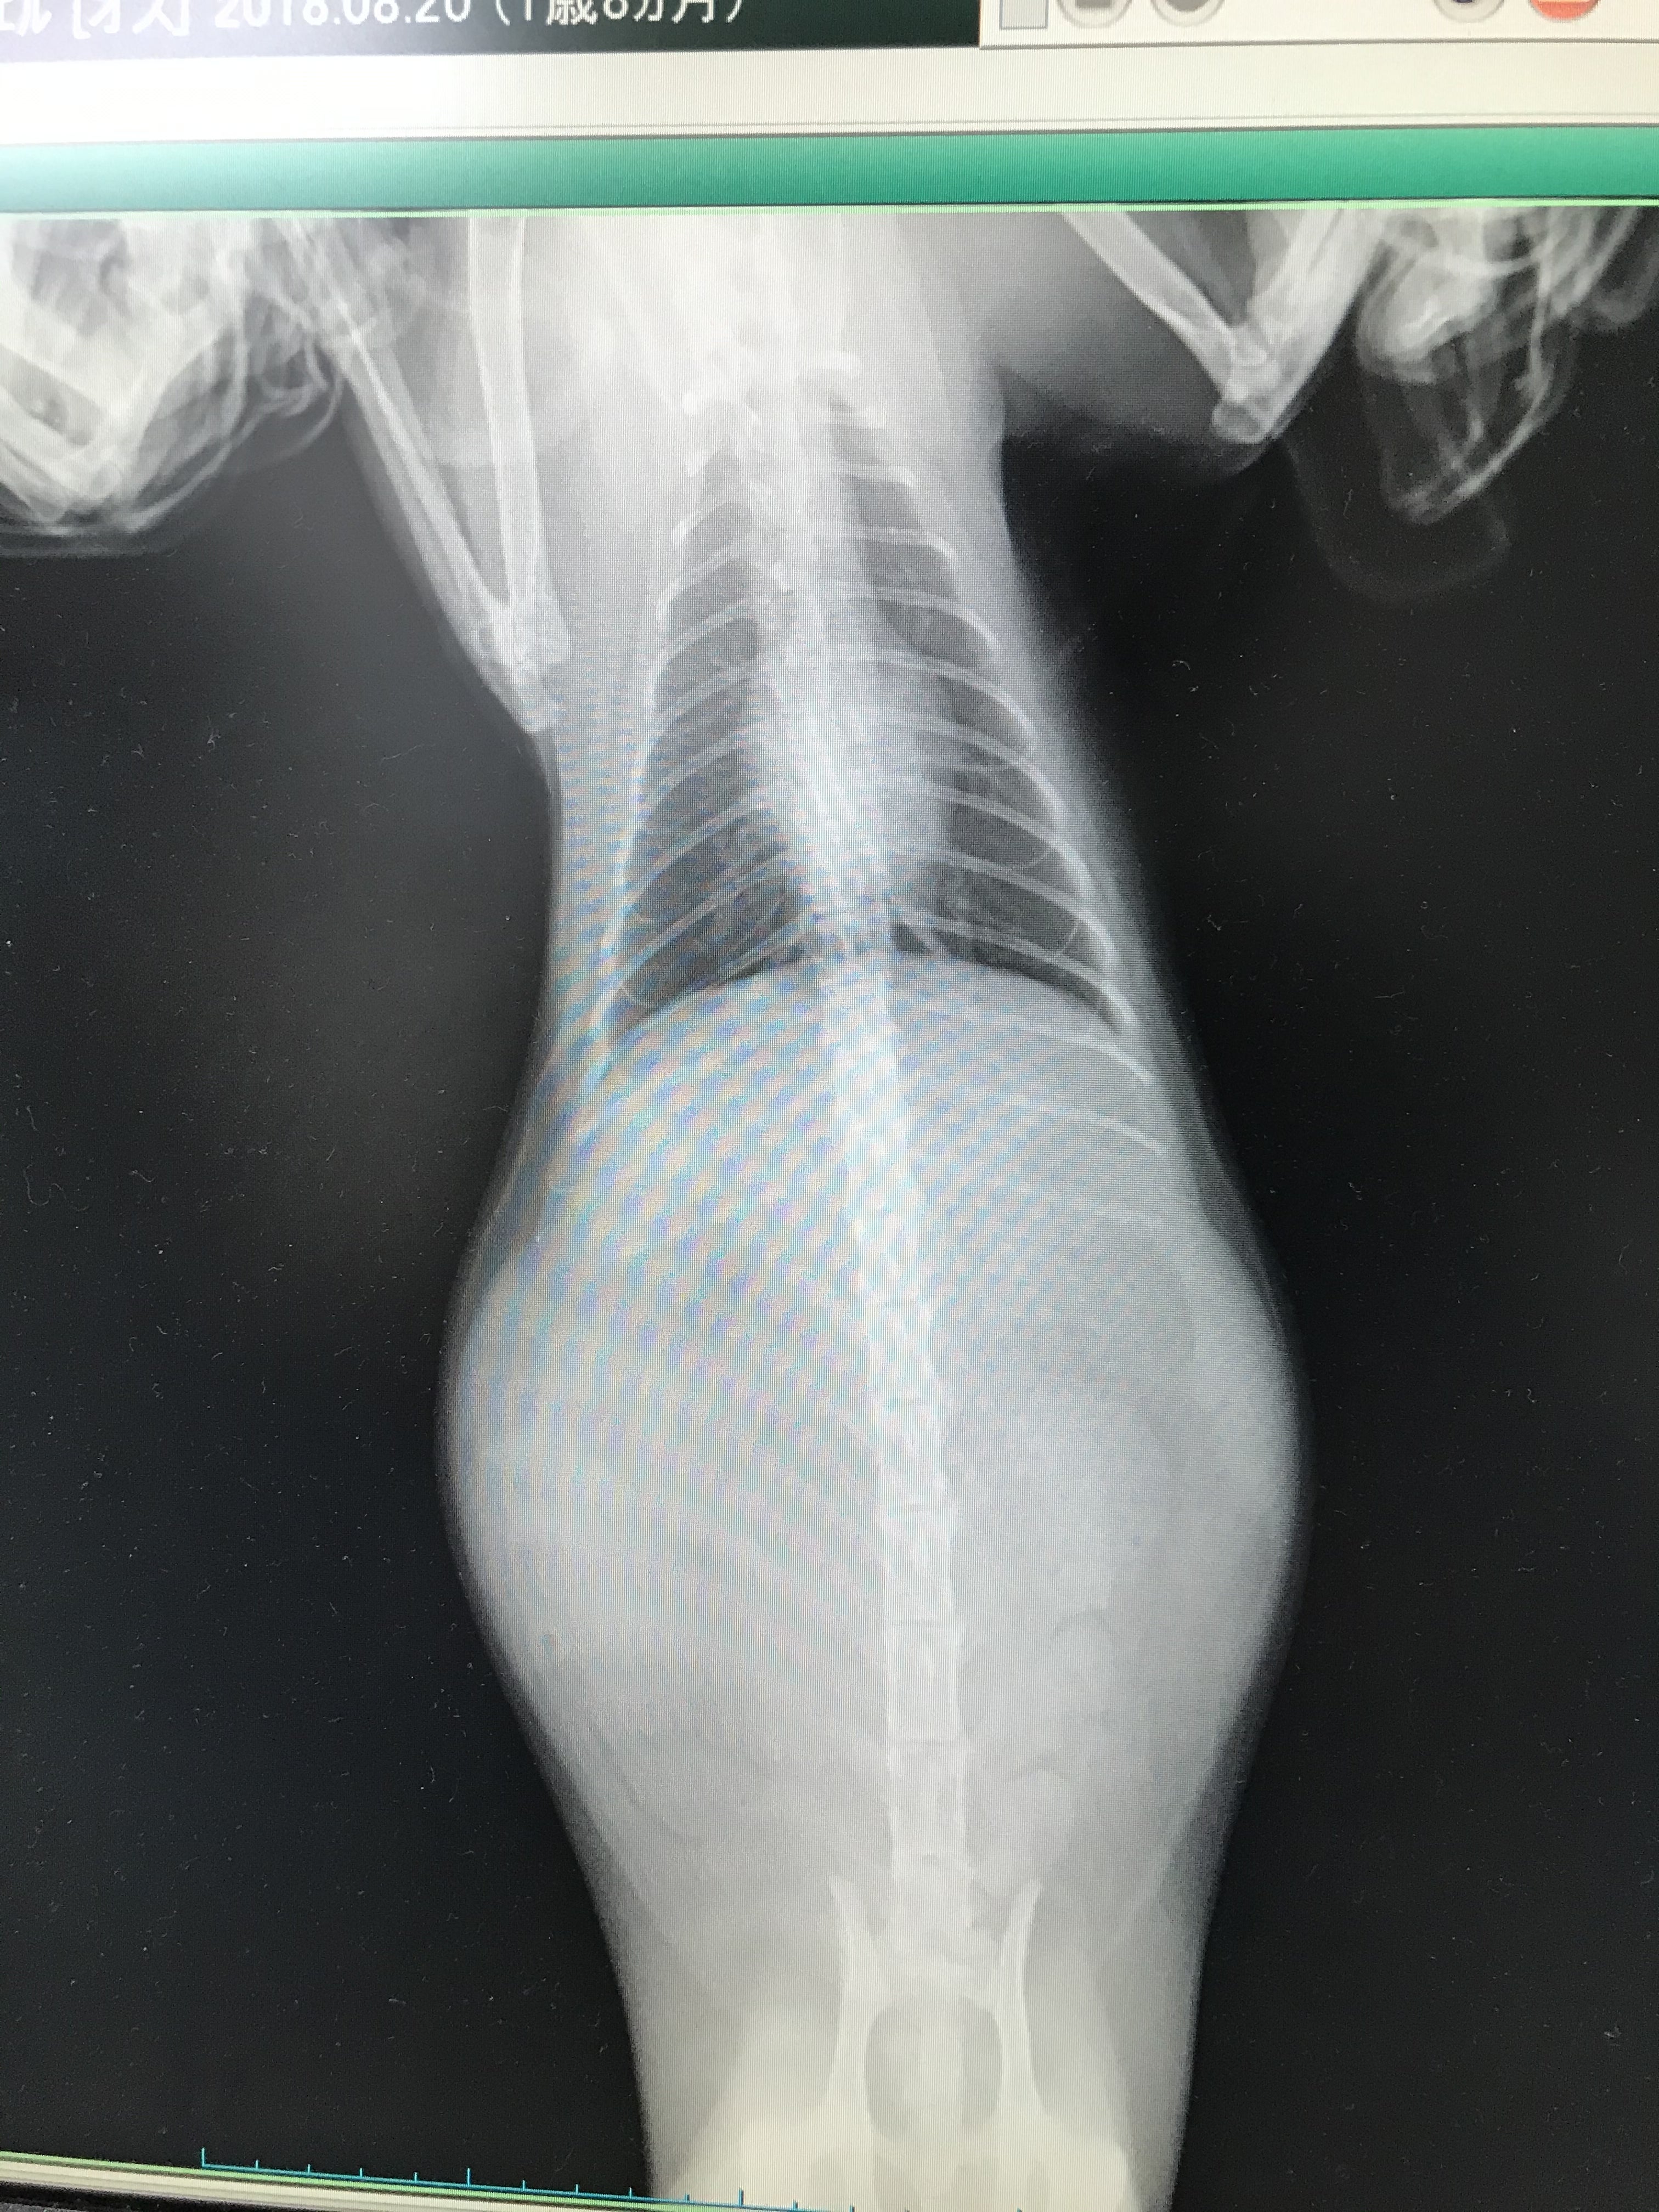

なかなか治らないのでエコー検査やレントゲン、血液検査での結果で

腹水がお腹に溜まり、FIPの疑い、血液検査でお医者様からFIP(ウェットタイプ)診断が下りました。

開始から4週間後の検査でA/G値、体重、貧血は改善が見られ、腹水も収まりエコー検査をしたところ、リンパ腺に炎症が見られるということでドライタイプの併発の可能性があるので投薬が550mgへ増量。